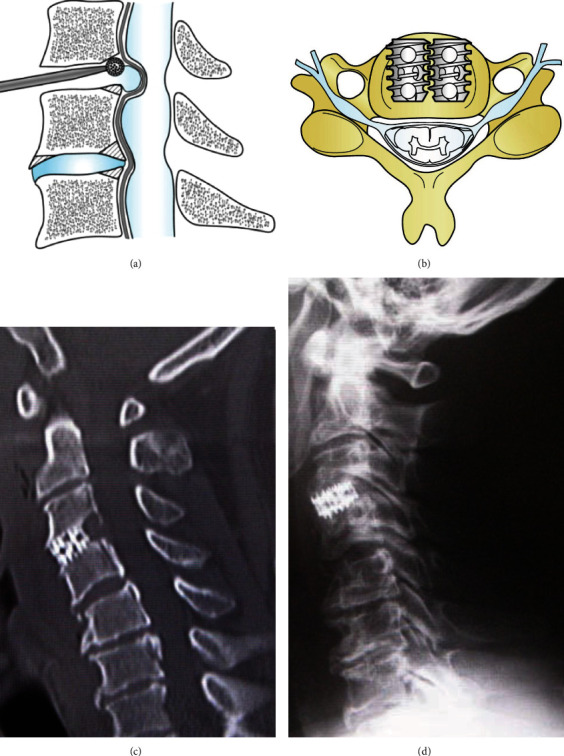

Bow hunter's syndrome is an ischemic manifestation of vertebrobasilar artery (VA) insufficiency due to stenosis or occlusion of the contralateral VA at the bony elements of the atlas and axis during neck rotation. In early reports, VA stenosis at the craniovertebral junction was the main cause, but later, symptoms due to VA occlusion at the middle and lower cervical vertebrae were also included in this pathology. Although the confirmed diagnosis is usually determined by dynamic digital subtraction angiography (DSA), we have experienced a method of minimally invasive MR angiogram (MRA) that provides the same diagnostic value as DSA and would like to present it here. The patient was a 61-year-old man who had been visiting the outpatient clinic for cervical spondylosis due to neck pain for 9 months. When he rotated his neck to the left side, dizziness and syncope appeared. Initial MRA in the neutral position did not show any steno-occlusive changes in the vertebrobasilar artery. In our hospital, repeated MRA with the neck rotated 45 degrees to the left demonstrated ipsilateral left VA severe stenosis. Subsequent DSA showed the same findings, with occlusion of the left VA. CT of the cervical spine revealed a ventral C3/4 osteophyte within the foramen. Based on these findings, instability at the C3-4 during head rotation was considered the cause of the vertebrobasilar insufficiency. The patient underwent anterior discectomy and fusion (ACDF) at the C3/4 level using a cylindrical titanium cage. Immediately after the surgery, the patient's symptoms improved dramatically and did not appear even when the neck were fully rotated to the left. More than 5 years have passed since the surgery, and the patient is still in good health.